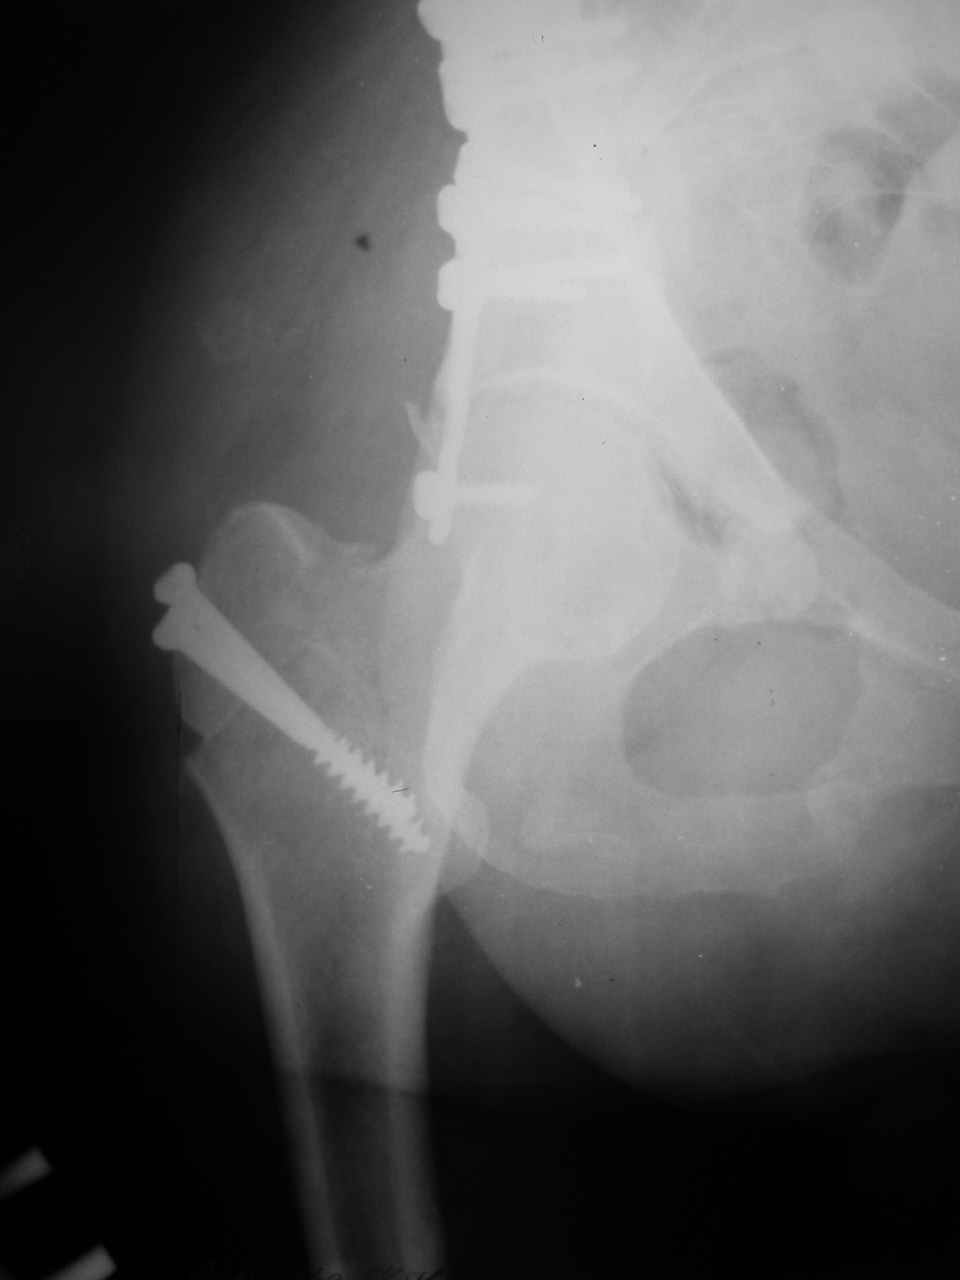

Сложностью, ассоциативностью характера перелома, я бы с радостью воспользовался мининвазивной перкутанной фиксацией винтами, но боюсь, что результат был бы ещё хуже, техникой непрямой репозиции перелома не владею, поэтому пытаясь получить анатомичную впадину приходится широко открывать, по крайней мере пока, а дальше буду пытаться уменьшать пространство...

Илеофеморальный доступ не совсем передний и сравнительно с илеоингвинальным, и Кохера-Лангенбека открывает весь наружный таз кроме самых передних отделов лонных костей, фиксацию которых я не ставил в задачу. Обширность диссекции, большая длительность операции и более высокий риск гетерооссификации - отрицательные моменты в обмен на возможность легче ориентироваться.

Комбинированные доступы - хорошая альтернатива, меньший процент осложнений, но я заметил , что без сбора *мозаики* безымянной кости сложно отрепонировать переднюю колонну, а с нерепонированной передней колонной невозможно анатомично собрать заднюю колонну и соотв. фрагменты стенки - так.что все равно открывать придется широко. Поэтому выбирая комбинированный

подход, передний доступ должен был бы быть продлен до задней трети крыла безымянной кости, а задний - практически до того же уровня, оставляя 6-7 см мостик. При этом вместо одного послеоп. рубца у больного остаются два сравнительно длинных.

Вопрос доступа к вертлужной впадине при остеосинтезе задача не простая. Конечно, у Летурнеля и Тайла всё давно описано, нам остается только брать на вооружение. Но сами понимаете, что не бывает двух одинаковых ситуаций, поэтому в каждом случае вопрос решается сугубо индивидуально. Наша главная цель - восстановить анатомию с нанесением минимальной дополнительной травмы тазобедреннному суставу, думаю с этим никто не поспорит. Расширенный илиофеморальный доступ уж слишком травматичен (как сказал один коллега "таз лежит отдельно, больной отдельно").Стоит ли делать из пациента анатомический препарат для того чтобы легче ориентироваться. Да и нужно ли собирать всю "мозаику"? Мы применяли при таких операциях своеобразную операционную хитрость - сначала устраняли грубое смещение крыла под гребнем с фиксацией так называемой "плавающей" пластиной (временно фиксированной на двух винтах)- доступ или продлевали боковой, или делали небольшой дополнительный разрез над гребнем. Это позволяло устранить грубое смещение и захождение отломков тела повздошной кости, что значительно облегчало репозицию и остеосинтез впадины над сводом. Основное внимание конечно же уделяли нагружаемому задне-верхнему отделу. Сообщите ваш адрес, пришлю схемы и рентгенограммы.